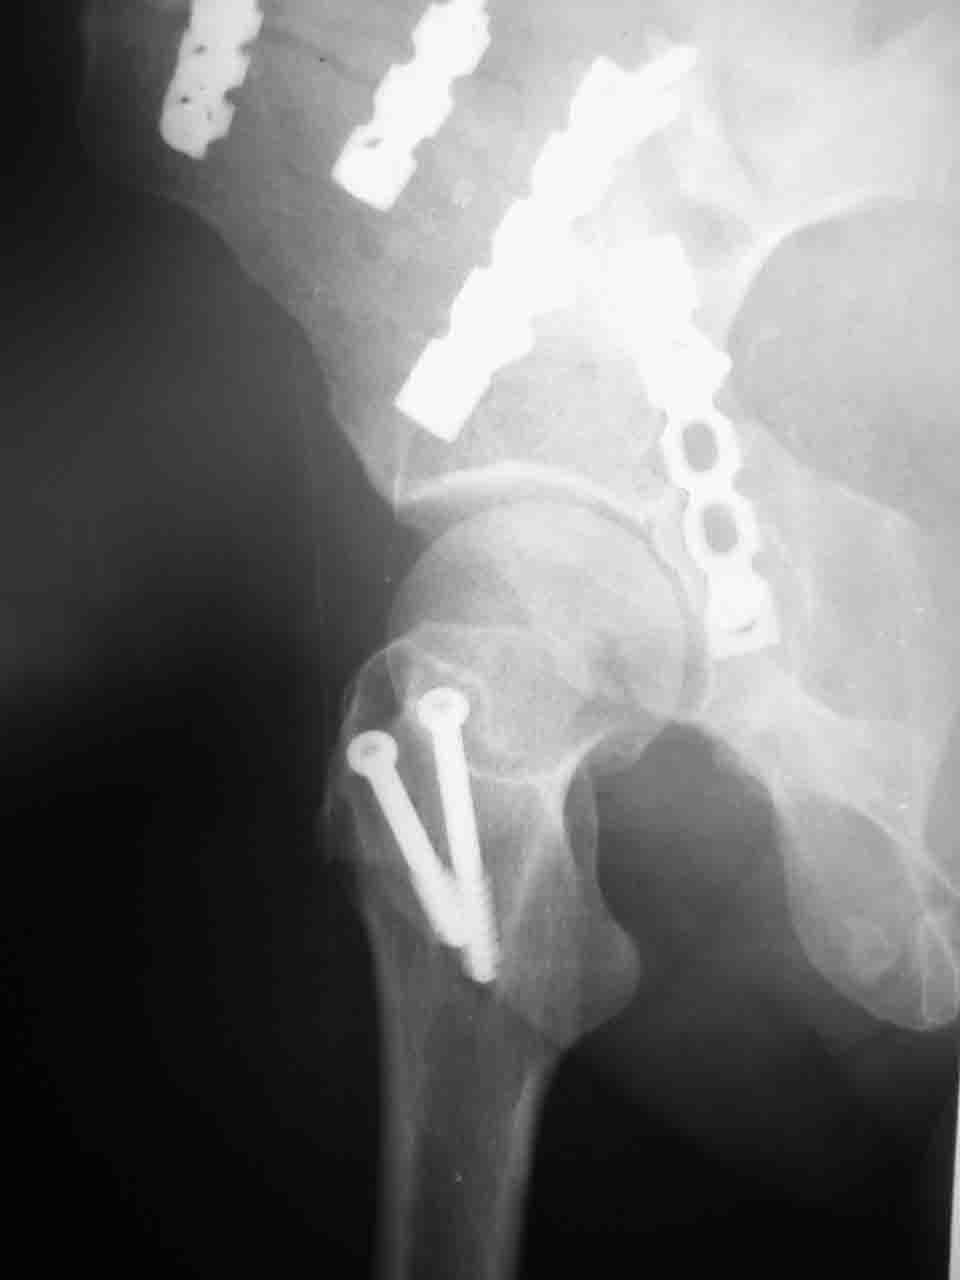

Re: Перелом вертлужной впадины

Снимки и схема